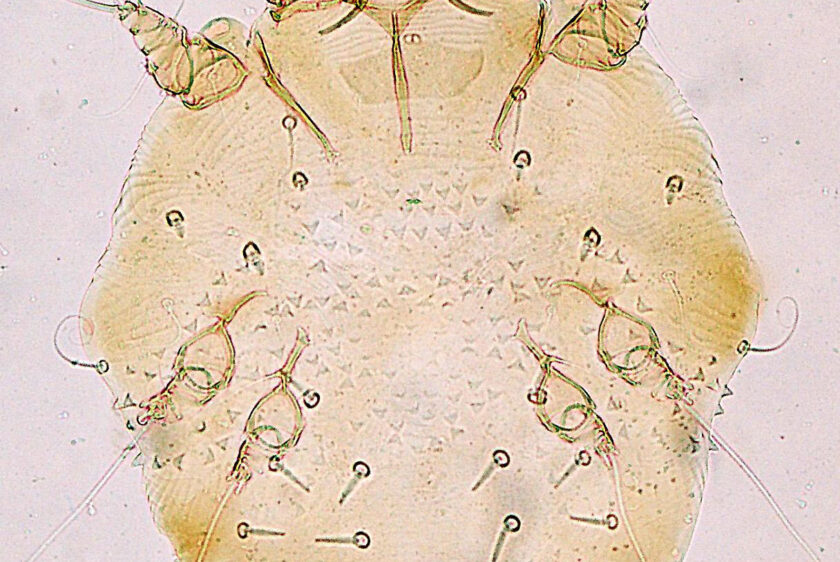

Ψώρα, μια επικίνδυνη δερματική νόσος, ιδιαίτερα μεταδοτική που προκαλείται από ένα παρασιτικό, που λέγεται άκαρι της ψώρας, (Sarcoptes scabiei)* το οποίο ζει και αναπαράγεται στο δέρμα του ανθρώπου, η ονομαζόμενη ψώρα (scabies), μια άκρως μεταδοτική νόσος. Είναι μικροσκοπικό αραχνοειδές παρασιτικό που προκαλεί έντονο κνησμό (φαγούρα ),προκαλείται έτσι τοπική φλεγμονή, με σοβαρές βλάβες στο δέρμα από το ξύσιμο άλλα και είσοδο βακτηριδίων που οδηγούν στην μορφή του Μολυσματικού κηρίου (του Κέλσου) , μια πολύ φλεγμονώδης μυκητιακή λοίμωξη. Αν και για πολλά χρόνια είχε σταματήσει να ακούγεται, με την εξάπλωση και στην Ελλάδα αυτής της ξεχασμένης νόσου, ξαναμπαίνει στη ζωή των σημερινών σύγχρονων κοινωνιών.